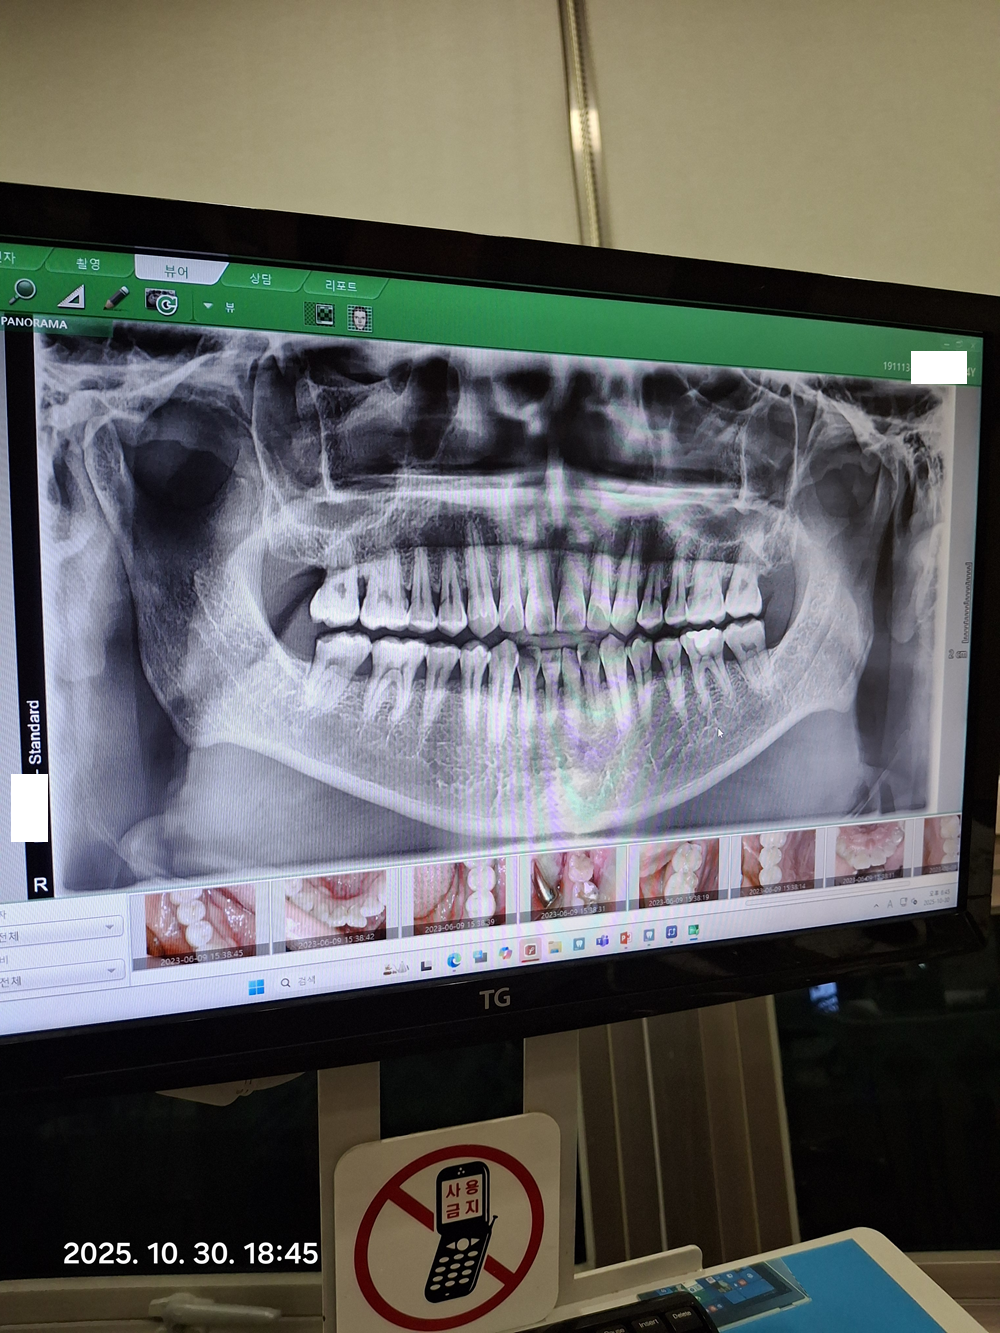

스케일링만 하면 X-ray 를 찍을 필요가 없지만 얼마전 단단한 걸 씹은 후로 어금니에 살짝 통증이 있어서 엑스레이도 찍었습니다.

아직 뽑은 이 없고 , 모두 내 치아들입니다. ^^

적당히 오래 살다보니 문제가 조금씩 있지만 아직은 버틸만 하네요.

부정교합? 확인을 위해서 뭔가를 씹으라고 해서 씹었더니 저렇게 착색이 되었더군요.

착색된 것은 치석을 제거하면서 닦아주었습니다.

크게 문제가 되는 것은 보이지 않고 , 깨진 이가 많은데 ( 이를 갈기 때문에... ㅠㅠ ) 크라운을 하는 것이 좋겠다고 합니다.

하지만, 꼭 할 필요는 없고 크라운을 씌워도 굉장한 효과를 보는 것은 아니라고 해서 그냥 더 버티기로 했습니다.